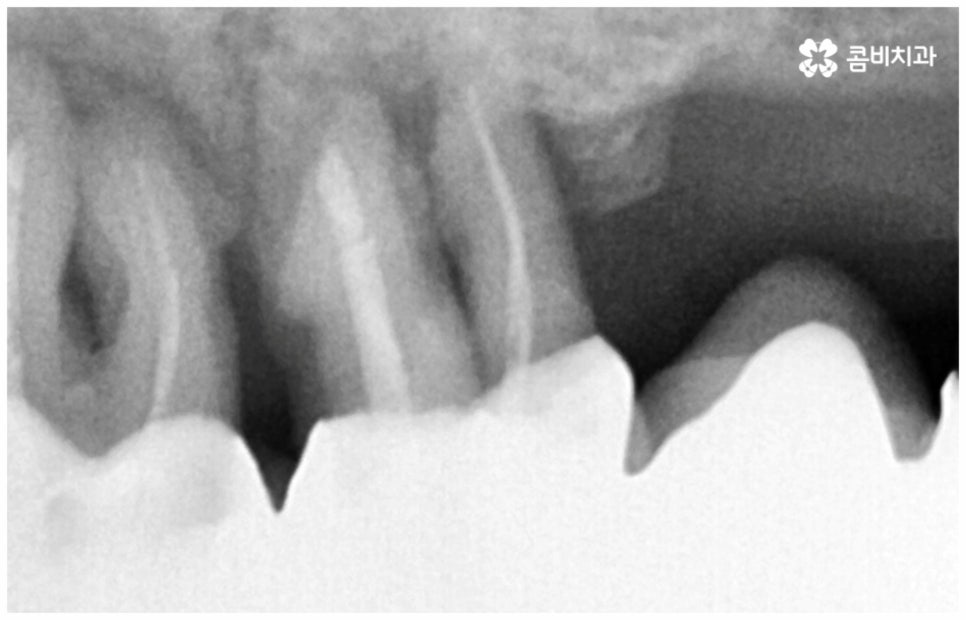

그러나 노화나 구강 질환을 원인으로 한 경우에는 식립 절차가 좀 더 복잡해 질 수 있는데요. 잇몸병을 예로 들어 생각해 보면 자연스러운 노화 및 관리 소홀로 인해 치아 주변 조직 (잇몸, 치주인대, 치조골 등) 에 염증 반응이 생기는 병인 치주 질환이 많이 심해졌을 때 상황에 따라 해당 자연 치아를 살리지 못하고 발치를 해야할 수도 있는 거예요. 이렇게 치주질환을 이유로 임플란트 식립을 진행할 때에는 식립 성공률을 높이고 임플란트수명 을 늘리기 위해 먼저 치주질환 치료를 선행해 줘야 하며, 환자분들의 상황에 따라 뼈이식 또는 상악동 거상술을 통해 잇몸뼈를 보충해 줘야 할 수도 있어요. 치조골이 이미 많이 녹아 있거나 병증이 극심하다면 임플란트 식립 난이도가 매우 높아지거나 때로는 불가능해 질 수 있기 때문에 다양한 임상 경험을 통해 풍부한 노하우를 가지고 있는 의료진에게 진단 및 치료를 받는 것이 굉장히 중요한 포인트라고 할 수 있습니다.